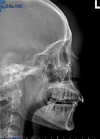

44

critique

petrous too low, by 10 deg (neck is extended) OML not perpendicular